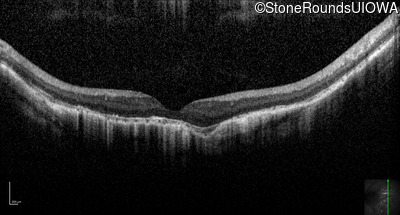

Optical Coherence Tomography - Left - 5/160

Exemplar / OCT Stack